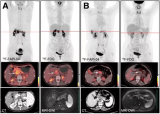

北肿-GrzmB靶向免疫PET探针转化研究

2024年10月10日,北京大学肿瘤医院李囡教授、杨志教授/基础医学院刘昭飞教授团队有关颗粒酶B靶向68Ga-grazytracer探针PET显像用于肿瘤免疫治疗疗效评估的研究在2024年10月Nature Communications正式发表。近年来,肿瘤免疫疗法在肿瘤治疗中取得了重大突破,但其有效性在不同患者以及不同肿瘤类型之间存在很大的差异。因此,早期预测肿瘤患者对免疫治疗的响应情况,对于改善患者的治疗预后至关重要。颗粒酶B作为免疫应答中最主要的效应分子之... 2024-10-14 核医学PET/CT靶向治疗

靶向TSPO分子探针18F-FDPA和18F-LW223用于兔腹主动脉粥样硬化易损斑块PET显像的对比研究

动脉粥样硬化易损斑块(VAP)破裂容易导致急性心血管事件。在斑块破裂前早期诊断VAP并有效干预是临床十分关注的问题。研究者们一直致力于开发性能优异的靶向相对分子质量1.8×104转位蛋白(TSPO)的探针,通过这类探针反映斑块中活化巨噬细胞数量,从而评价VAP。首都医科大学附属北京安贞医院李全等对2种新的TSPO靶向探针——18F-FDPA和18F-LW223,进行对比研究。通过在腹主动脉VAP兔模型中开展实验,该研究发现18F-FDPA可对易损斑块进行... 2024-09-25 核医学靶向治疗